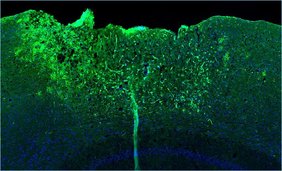

Die sternförmigen Gliazellen spielen außerdem eine Schlüsselrolle bei der Vernarbung von verletztem Hirngewebe. „An der geschädigten Stelle umschließen Astrozyten den Wundkern. So begrenzen sie weitere neurodegenerative Prozesse und unterstützen die Heilung“, erläutert Professorin Leda Dimou. Die Leiterin der Abteilung Molekulare und Translationale Neurowissenschaften an der Klinik für Neurologie war an der Studie federführend mitbeteiligt. In unmittelbarer Nähe der Verletzung fanden die Forschenden eine auffällige Genexpressionssignatur – ein Hinweis auf eine besonders hohe Aktivität von NF-κB in Astrozyten. Um den Einfluss dieses Genschalters genauer zu untersuchen, arbeiteten die Forschenden mit Mausmodellen. In diesen war NF-κB in Astrozyten entweder dauerhaft aktiviert oder stark gehemmt. Das Team wollte wissen: Verbessert oder verschlechtert sich dadurch die Heilung nach einer traumatischen Hirnverletzung?

Das Ergebnis fiel eindeutig aus: War NF-κB dauerhaft aktiv, reagierte das Immunsystem schneller und stärker auf die Verletzung. Diese überschießende Neuroimmunantwort löste Entzündungsprozesse aus und störte sowohl Wundheilung als auch Narbenbildung.

„In den Wundbereich wanderten plötzlich auch bestimmte Immunzellen wie dendritische Zellen ein. Dadurch konnte sich kein stabiles Narbengewebe bilden, was schließlich zu neurologischen Defiziten führte“, berichten die Erstautorinnen der Studie, Tabea M. Hein und Ester Nespoli. Erstaunlich: Ganz ähnliche Prozesse zeigen sich im alternden Gehirn. Wurde NF-κB in Astrozyten dagegen gehemmt, waren einzelne positive Effekte zu beobachten: So verbesserten sich die antioxidative Abwehr und die Funktion der Mitochondrien. „Diese Veränderungen reichten jedoch nicht aus, um den Heilungsprozess insgesamt deutlich zu verbessern“, erklären die Forschenden.